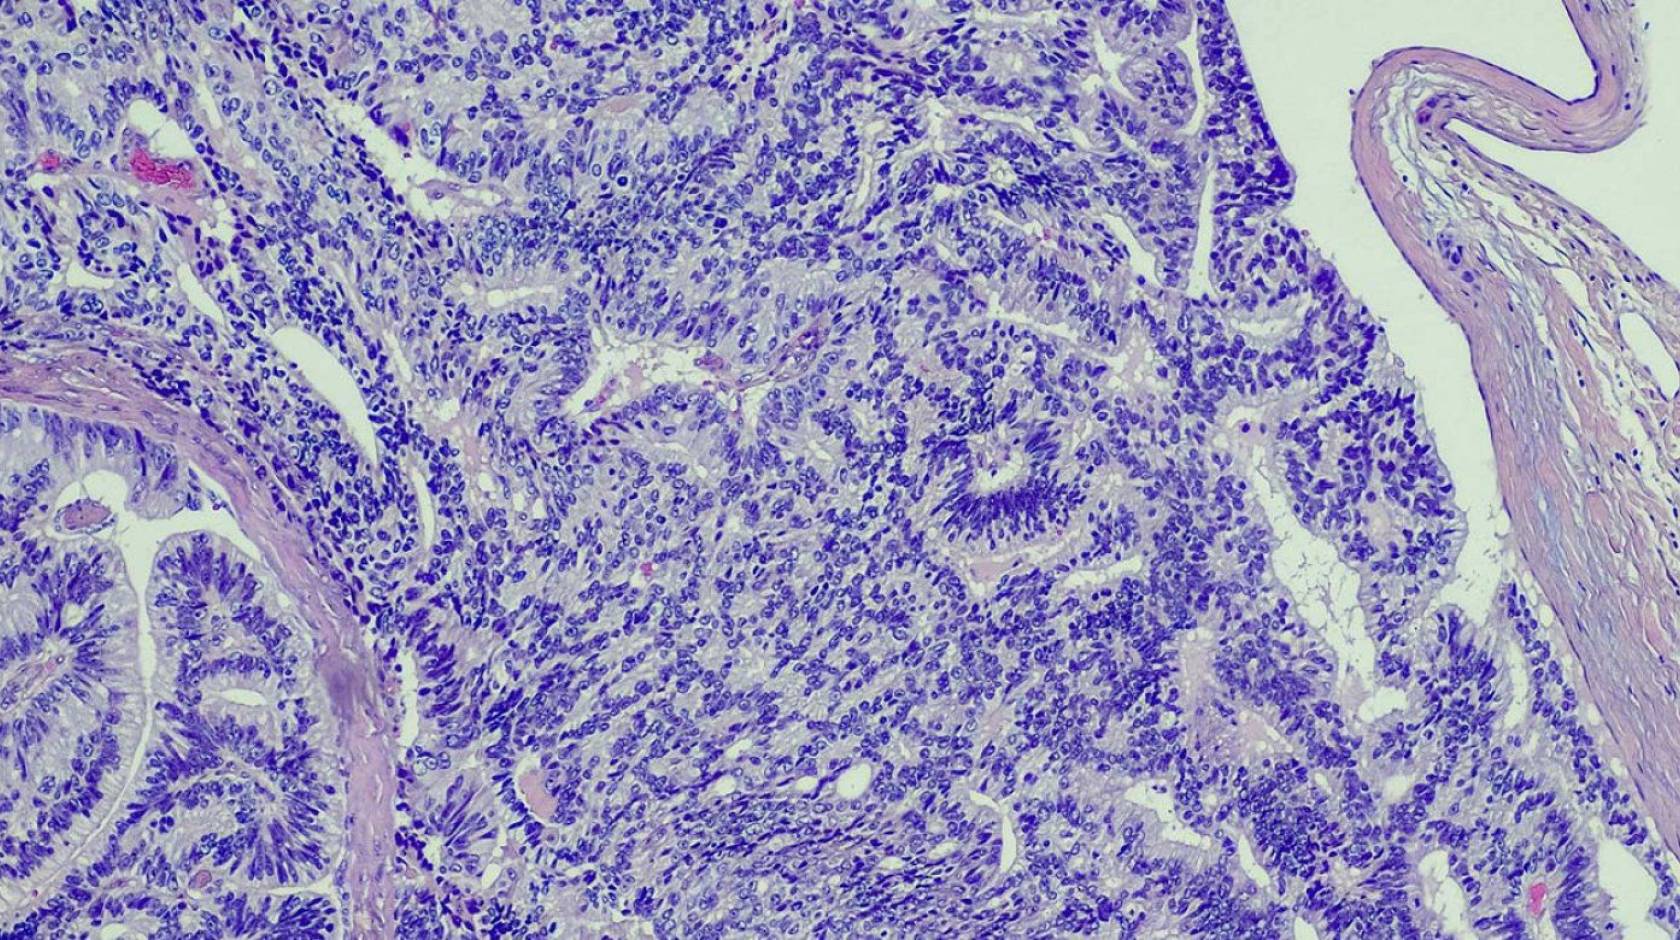

There have been multiple alternatives proposed over the years. The alternative that seems to have the most traction among clinicians and pathologists is “acinar neoplasm,” which describes GG1 as an abnormal growth visible under the microscope, but not one with the potential to spread or kill.